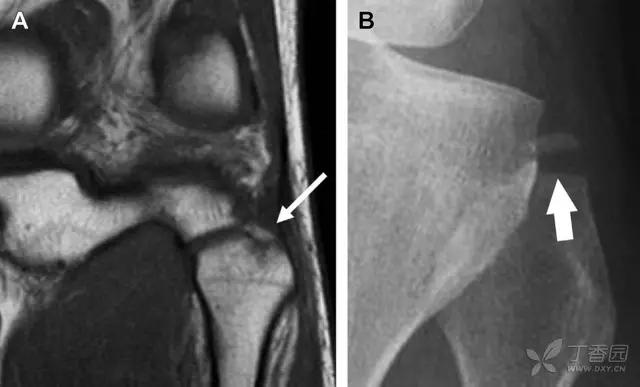

10 胫骨后外侧碎片骨折

胫骨后外侧小片骨皮质的压缩性骨折,可能是旋转移位损伤的唯一证据(图 3)。这种骨折在常规膝关节平片很难发现,若怀疑存在骨折,行下肢内旋斜位片检查可诊断。

图 3 胫骨后外侧碎片骨折

A 正位片示胫骨后外侧处可见一压缩骨折的小碎片(方框)。这是胫骨撞击股骨外侧髁旋转移位时所致。B 另一位患者的 MRI 矢状位 T1 加权像示胫骨后外侧骨折碎片(箭头)。